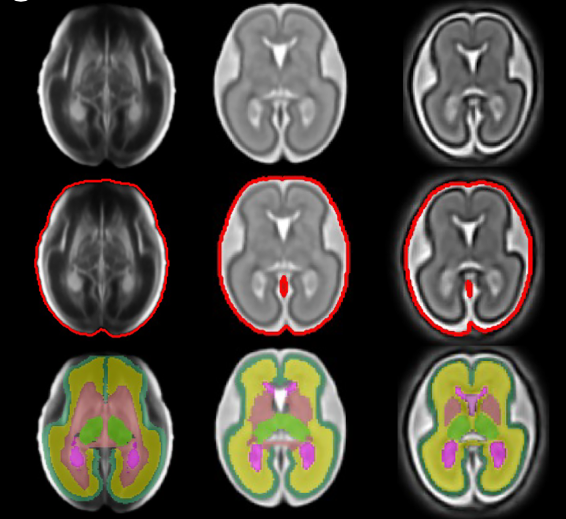

BEAN: Brain Extraction and Alignment Network for 3D Fetal Neurosonography

Subcortical segmentation of the fetal brain in 3D ultrasound using deep learning